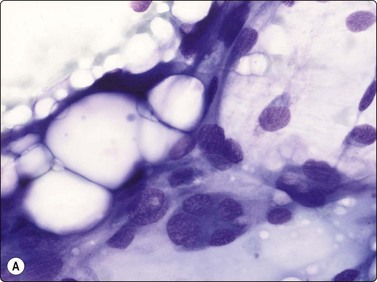

Pleomorphic liposarcoma resembles the pleomorphic sarcoma of MFH type cytologically. The diagnosis rests on the presence of highly atypical, sometimes multinucleated lipoblasts. Lipoblasts in liposarcoma smears may be univacuolated and resemble signet ring cells or they may be multivacuolated, containing small or large vacuoles or a mixture of both. The scalloped nucleus is an important cytologic feature (Fig. 15.29). In FNB smears, superimposed fat vacuoles from adjacent fat tissue may produce artifacts in other cell types, causing a resemblance to lipoblasts, and macrophages in adipose tissue showing inflammatory or reactive changes may have a vacuolated cytoplasm (lipophages). An infrequent diagnostic pitfall is soft tissue metastasis of renal cell carcinoma. It is important to remember that the majority of liposarcomas are deep seated and only infrequently subcutaneous. The cytologic feature of liposarcoma in FNB smears have been investigated in several series.32,42-45

image

Fig. 15.29 Pleomorphic liposarcoma

Poorly cohesive cells with pleomorphic rounded nuclei and irregular nuclear chromatin; note multivacuolated lipoblasts with scalloped nuclei (MGG, HP).